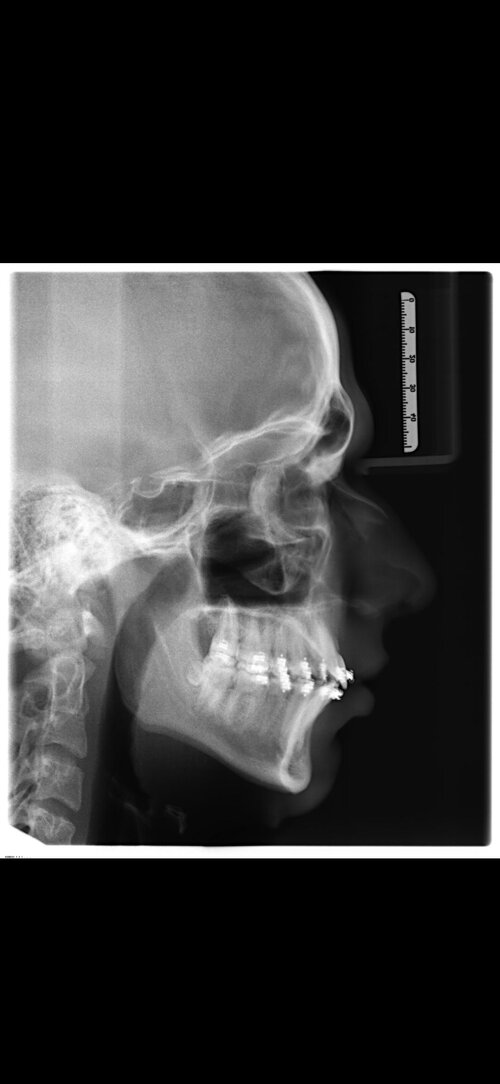

I'm getting bimax + genioplasty in 3 days at age 17. I'm scared of underadvancement, i get it performed by Dr Kater, he's very experienced but also rather conservative. I'm having a last consultationtalk with him 1 day before surgery, any ideas on how i can convince/show him, that i want more advancement and i'm not scared of big changes. Are pictures of good results the way or is that just gonna diminish my credibility?